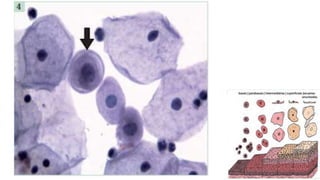

Citoplasma relativamente abundante, delicado,

semitransparente, que cora fracamente em azul, às vezes com

vacúolos.

Os núcleos são redondos ou ovais, com alguma variação do

tamanho, cromatina finamente granular exibindo cromocentros

ou nucléolo.

Quando as células são vistas lateralmente, assumem a forma

colunar alta característica, com núcleo oval, localizado na

região basal. Nessa perspectiva, quando em conjuntos,

constituem os arranjos conhecidos como “fila”, ou “paliçada”.

Quando as células são vistas de frente, elas se agrupam em

conjuntos monoestratificados, perdem a sua forma colunar e

apresentam, às vezes, bordas citoplasmáticas bem definidas,

lembrando um “favo de mel”. Os núcleos arredondados

mostram polaridade conservada (a distância entre os núcleos

é relativamente constante, não ocorrendo sobreposição

nuclear).